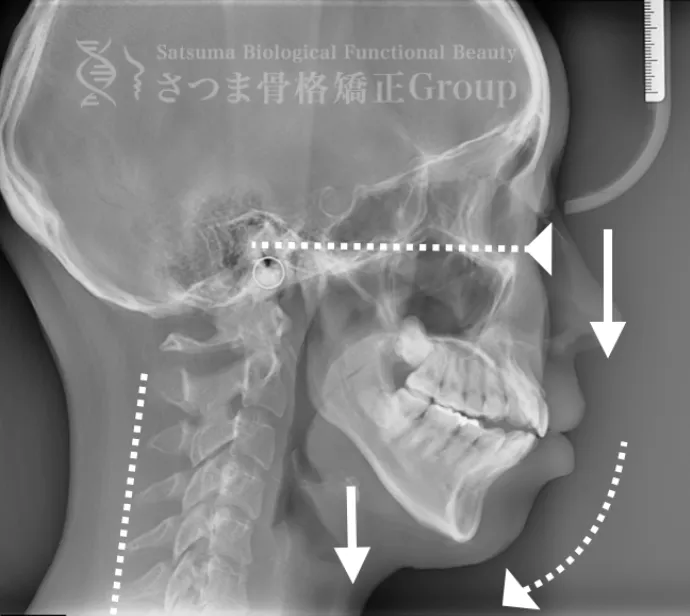

渋谷TMJ歯科クリニックでは、頭蓋および頸椎の歪みが顎位(あごの位置)と咬合(噛み合わせ)の乱れを引き起こし、その結果として顔の歪み、顎関節症、食いしばり、ストレートネックによる強い肩こり、さらには自律神経の乱れへとつながると考えています。

これらの問題を正確に評価するため、当院では セファロシステムによるレントゲン撮影(X-ray images) を行っています。

セファロ撮影によって 顎関節・頭蓋骨・頸椎の位置関係を客観的に可視化でき、施術前の状態を科学的に把握することが可能となります。

施術の前後で撮影したレントゲン写真を比較することで、改善の度合いや変化を一目で確認できます。